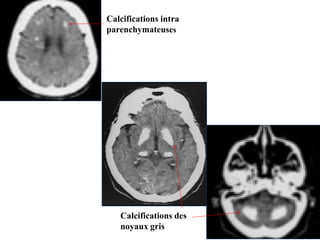

1- Hématome intra parenchymateux spontanément

hyperdense

2- Œdème hypodense

1

2

Calcifications intra

parenchymateuses

Calcifications des

noyaux gris